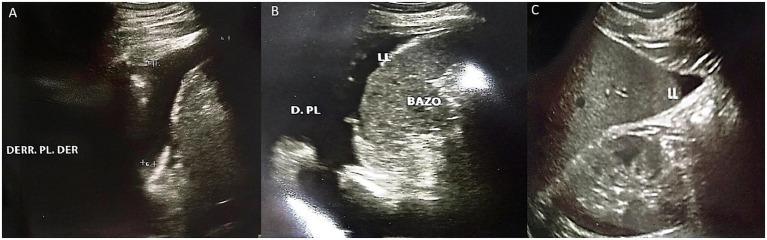

A 54-year-old male patient suffered a snakebite from the Viperidae family 24 h ago, on his right upper limb. Classified as moderate envenomation, he was given antivenom and admitted to the hospital. During his stay, he began to show clinical and paraclinical alterations, including sinus bradycardia on the electrocardiogram and acute renal injury, requiring dialysis therapy sessions. In daily ECG controls on day 13, the heart rate normalized. However, after day 22, he was discharged but remained under triweekly dialysis therapy.

一名54岁男性患者于24小时前在其右上肢被蝰蛇科蛇咬伤。被分类为中度中毒,给予抗蛇毒血清并入院治疗。在住院期间,他开始出现临床和辅助检查异常,包括心电图显示窦性心动过缓和急性肾损伤,需要进行透析治疗。在第13天的每日心电图检查中,心率恢复正常。然而,在第22天后,他出院了,但仍需每三周进行一次透析治疗。